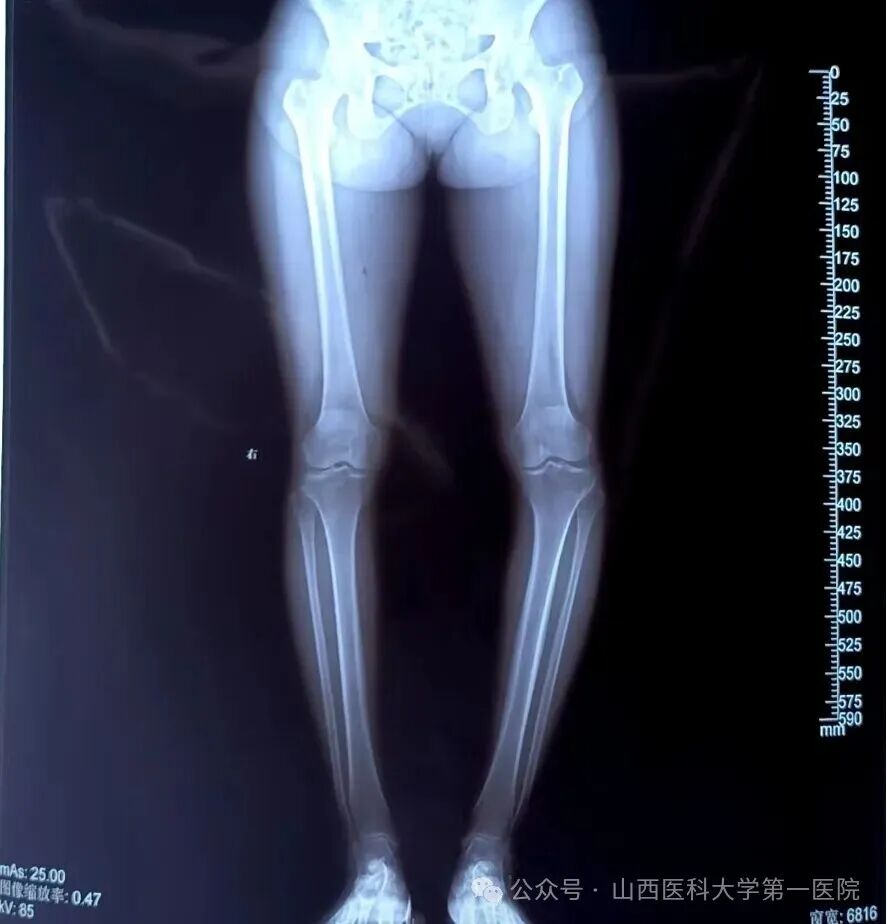

胫骨高位截骨术(HTO)是治疗单间室膝关节骨性关节炎的有效手术方式,尤其在年轻且运动活跃的患者中被广泛应用。HTO是通过矫正下肢机械轴力线从而达到缓解单侧膝关节间室疼痛的症状。传统HTO手术过程中出现即使细微的冠状面矫正误差也能明显改变膝关节的负重分配。因此,精确的下肢机械轴矫正是HTO成功的关键之一。

术后左下肢力线明显矫正